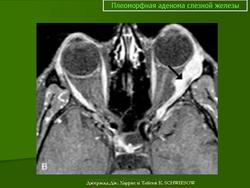

При рентгенографии выявляют увеличение полости орбиты вследствие истончения и смещения кверху и кнаружи ее стенки в области слезной ямки. Ультразвуковое сканирование позволяет определить тень плотной опухоли, окруженной капсулой, и деформацию глаза. При компьютерной томографии опухоль визуализируется более четко, можно проследить целость капсулы, распространенность опухоли в орбите, состояние ее прилежащих костных стенок. Лечение только хирургическое. Прогноз для жизни и зрения в большинстве случаев благоприятный, но пациента следует предупредить о возможности рецидива, который может возникнуть через 3—45 лет. Приблизительно у 57 % больных при первом же рецидиве обнаруживают элементы озлокачествления. Опасность злокачественного перерождения плеоморфной аденомы возрастает по мере увеличения периода ремиссии.